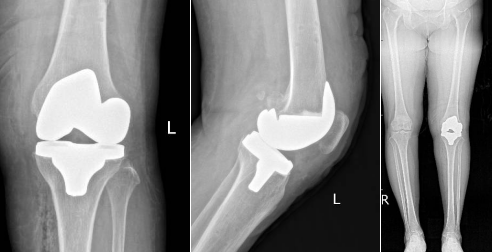

術后患者的關節(jié)力線恢復平衡

患者術后DR